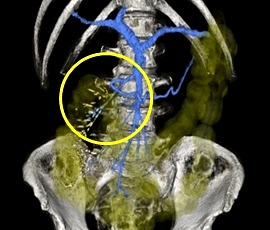

約6年前より繰り返す右側腹部痛と下痢を主訴にて精査目的に受診。腹部レントゲン検査にて、右側結腸の腸間膜側に一致した石灰化を認め、精査の結果、典型的な結腸辺縁静脈の石灰化と診断。手術(腹腔鏡下結腸切除術)を施行した。病理診断結果は、静脈硬化性大腸炎であった。

CT画像

CT(3D)画像